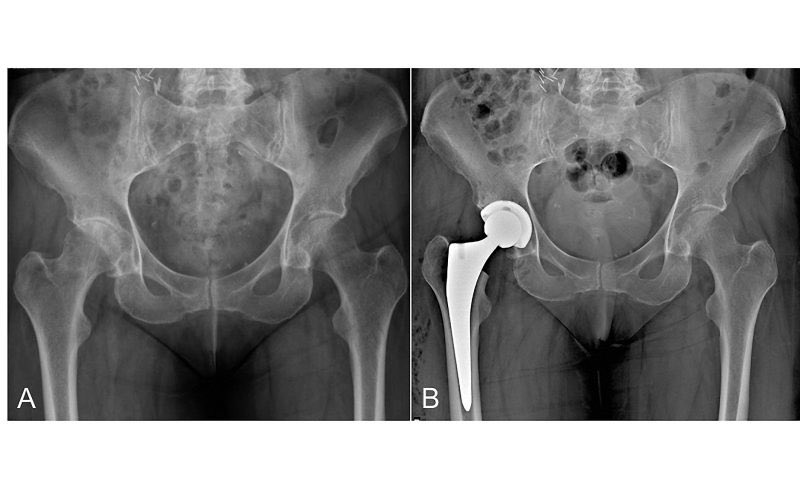

يبدأ علاج خشونة الورك بالعلاج التحفظي، وفي حال عدم تحسن المريض مع وجود مراحل متقدمة في الاحتكاك فيكون الحل في العلاج الجراحي، وهو عبارة عن استبدال كامل لمفصل الورك بواسطة المفاصل الصناعية. حيث تعتبر من اكثر العمليات نجاحاً وبنتائج مذهلة